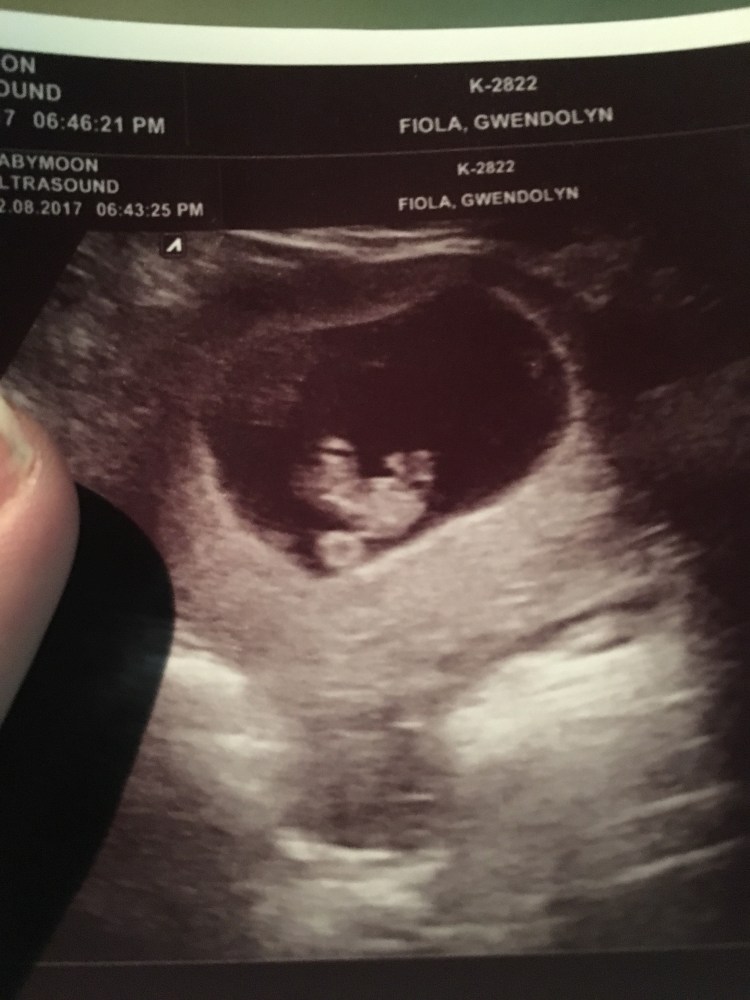

Another great change is I am a lot more laid back this pregnancy. With November I Googled every single symptom and was pretty freaked out about having a miscarriage. This pregnancy I have been too busy to worry that much and have trusted my body. It also helps me knowing what round ligament pain feels like and to know it’s normal. Rob was anxious to announce but I wanted to wait till at least our 9 week elective ultrasound to see a heart beat since that makes miscarriage rates drop below 5%. Seeing that sweet baby and hearing the heartbeat made my mama heart so happy! Since then we have also recently heard the heartbeat at my OB’s office.

9 week baby